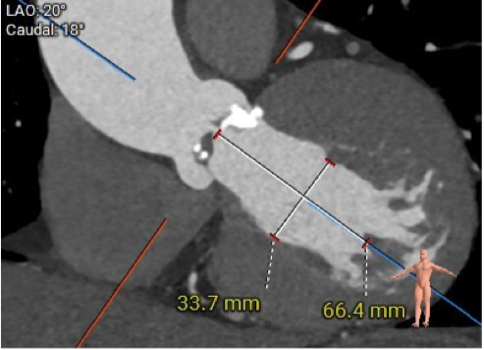

此患者解剖结构复杂:1)升主动脉明显增宽,平均直径达到54.5mm。

该结构需谨慎评估血管夹层和破裂风险,对瓣膜系统的通过性能要求极高。

2)患者主动脉根部结构复杂,为Type 2型二叶瓣畸形,左右对合缘、右无对合缘处均可见钙化融合嵴,瓣环平面可见严重钙化,左冠窦底钙化灶延伸至左室流出道,且左室腔小。

瓣叶钙化严重,且增厚增长。